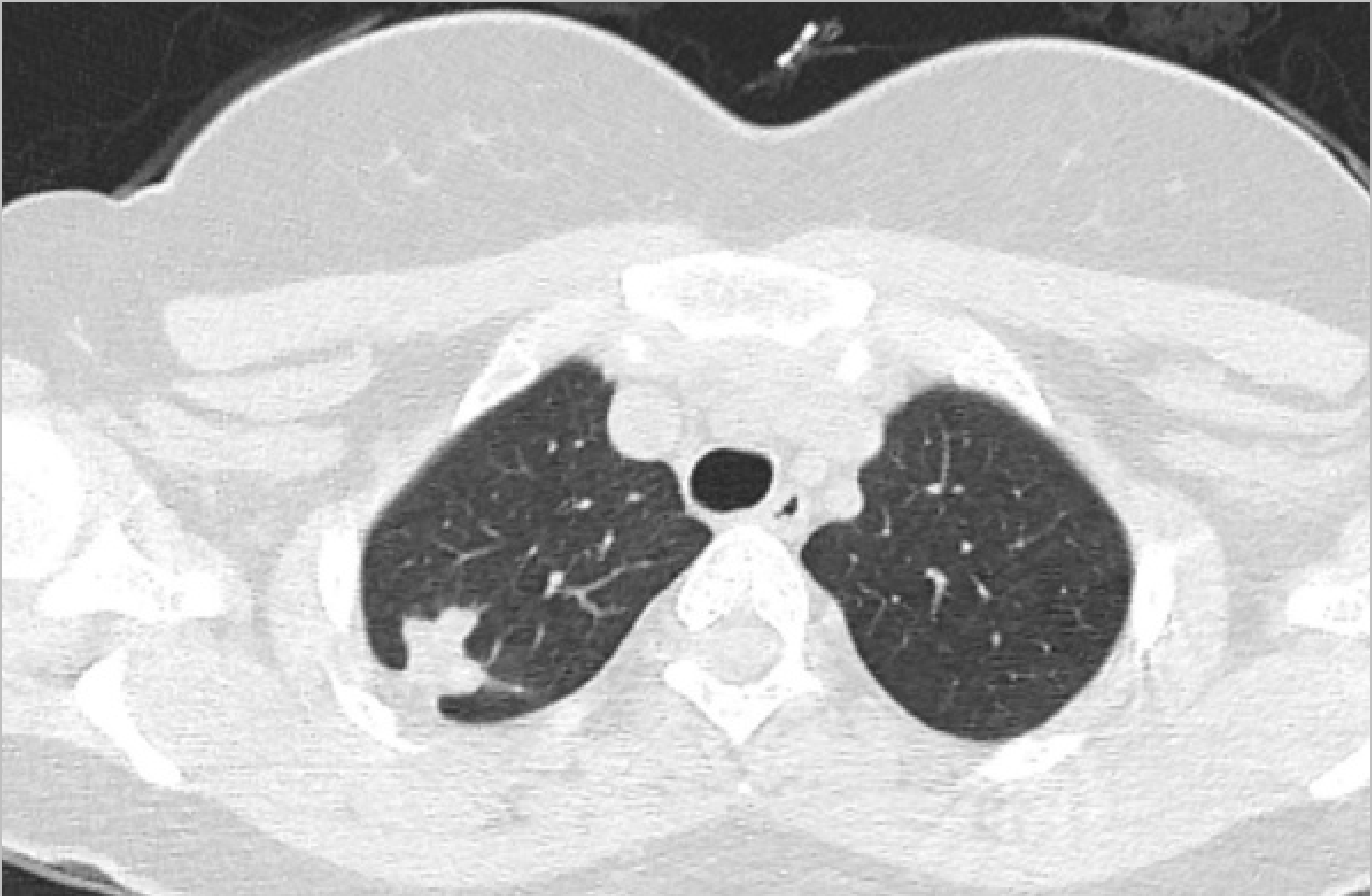

A young asymptomatic woman was referred after an incidental right upper lobe pulmonary nodule was discovered during routine screening. CT thorax revealed a 17 × 15 mm subpleural nodule with lobulated margins and focal calcification, raising suspicion for a tubercular granuloma in this healthcare worker from a tuberculosis-endemic region.

CT Axial

CT Coronal

Advanced bronchoscopy was performed using augmented fluoroscopy with cone beam CT (CBCT) confirmation of tool-in-lesion, followed by transbronchial cryobiopsy with a 1.1 mm cryoprobe. The procedure was uneventful.

Histopathology demonstrated features consistent with a benign pulmonary hamartoma, while microbiological testing including GeneXpert, AFB smear, fungal smear, and bacterial cultures was negative.

This case highlights that pulmonary hamartomas can radiologically mimic tubercular granulomas. It also underscores the value of CBCT-guided bronchoscopic navigation and cryobiopsy in safely obtaining diagnostic tissue from peripheral pulmonary lesions, helping avoid unnecessary anti-tubercular therapy.